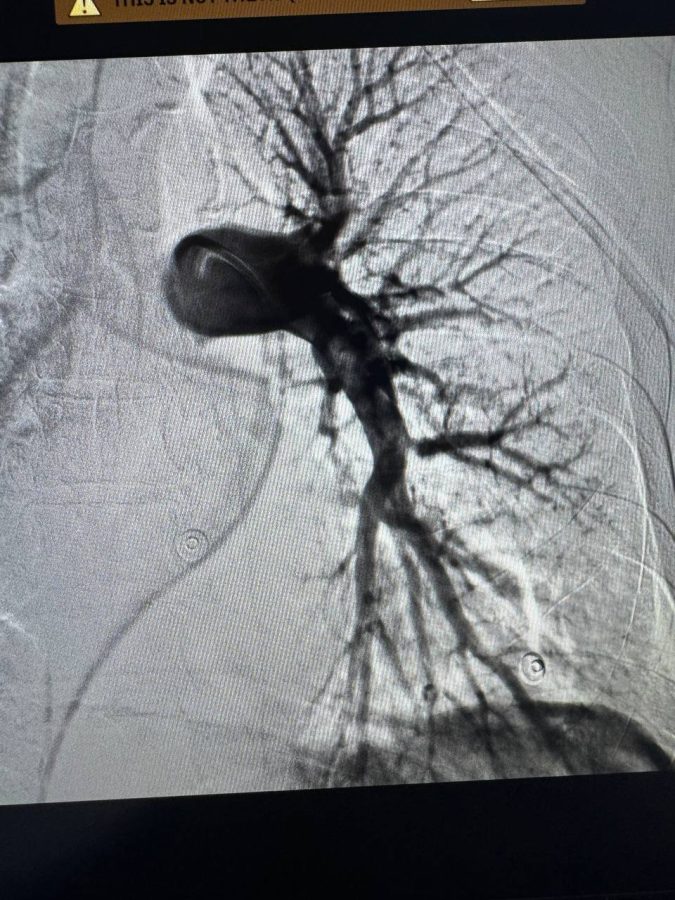

У Лікарні Святого Пантелеймона Першого медоб’єднання Львова вперше у західних областях України провели ендоваскулярну тромбаспірацію – сучасну процедуру з видалення тромбів із легеневої артерії без розтину грудної клітки. Про це повідомили у пресслужбі медзакладу.

Медики оперативно провели малоінвазивне втручання: тромби видалили через судину під рентген-контролем, без відкритої операції. Увесь час пацієнт перебував при тямі й спілкувався з командою лікарів. Уже на п’ятий день після операції його виписали додому без ускладнень.